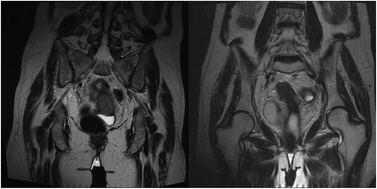

Cervical cancer is the fourth-most common type of cancer and cause of death in women. Human papilloma virus (HPV) infection is responsible for over 90% of cervical cancers. The recommended treatment is multidisciplinary, consisting of a combination of surgery, chemotherapy, and radiation therapy. The standard treatment in advanced stages, such as FIGO IIIb, is radio-chemotherapy with overall 5-year survival of 32%. Photofrin II has been demonstrated to serve as a specific and selective radiosensitizing agent in both in vitro and in vivo tumor models, admitted for radiation therapy. We describe a patient with advanced cervical carcinoma (squamous cell) who contacted us for further therapy in 2003. Staging included a gynecological examination, colonoscopy, explorative laparotomy, biopsy and pelvic MRI. The explorative laparotomy showed enlarged pelvic and para-aortal lymph nodes. The histologic examination described tumor infiltrated, positive lymph nodes (Stage FIGO IIIb). Contrary to recommendations, the patient refused standard treatment with a combination of chemotherapy and radiotherapy, but accepted a combined treatment of Photofrin II as a radiosensitizer and a radiotherapy procedure. She underwent irradiation with a 50.4 + 14 Gy boost with fractionation of 1.8 Gy day−1 for 5 days per week; the boost was given with 2 Gy fractions. She was injected with a single intravenous dose in a slow infusion (30 min) of 1 mg kg−1 of Photofrin II 24 h prior to radiation therapy. A localized relapse in the cervix appeared after 30 months, and was resected by hysterectomy. The patient is still alive with no evidence of disease after 15 years.